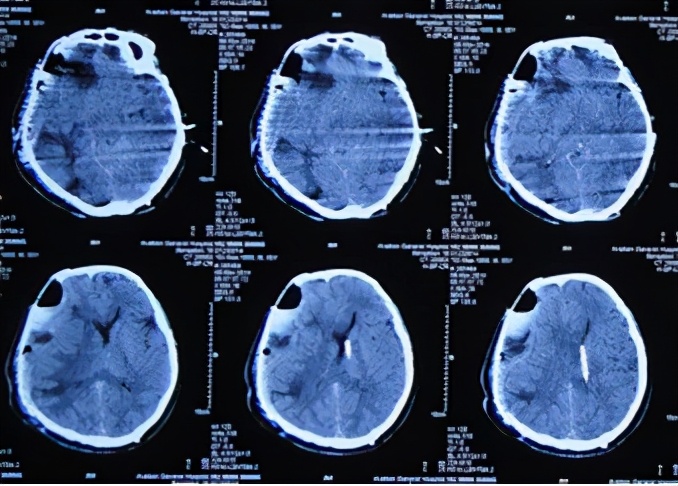

术后,患者减压窗张力持续偏高,并于2013年9月20日即开颅术后第3天,切口出现渗液红肿,给予抗感染及切口换药处理,并行切口分泌物细菌培养(注:2天后报告为阴沟肠杆菌生长)。于开颅术后第4天和第5天即2013年9月21日和9月22日两次行腰椎穿刺,均提示脑脊液压力升高明显。开颅术后第8天即2013年9月25日,行头CT检查:脑膜脑膨出较前加重(图-3),而且这期间头部切口感染仍进行性恶化,且体温升高至39℃以上、颈部僵硬,意识障碍逐渐加重等表现。

图-3:2013年9月25日头CT

于2013年9月29日即开颅术后第12天(转院后第4天),转至北京某著名的某三甲医院,入院当日行头CT检查:脑膨出及脑肿胀均严重(图-4)。

图-4:2013年9月29日头CT